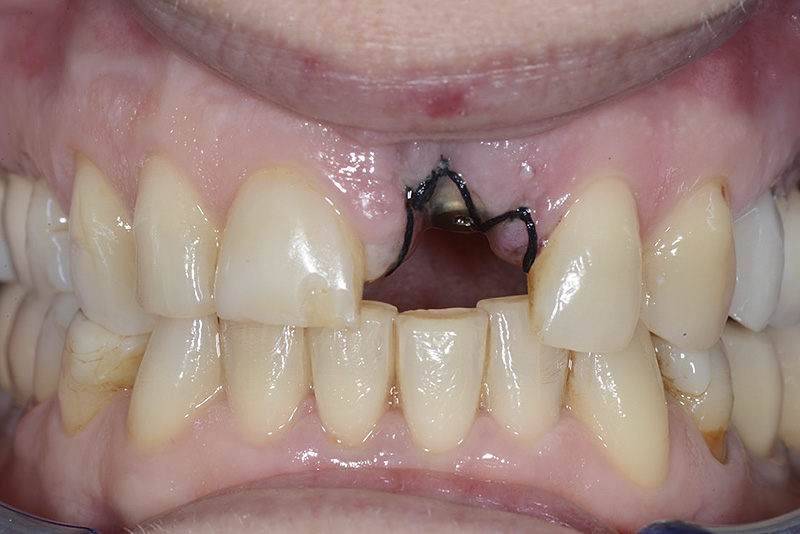

PREMESSA: in seguito all’estrazione dell’incisivo laterale superiore di destra, resasi necessaria per cause batteriche, si decide di affrontare il caso con il posizionamento di un impianto in sostituzione dell’elemento mancante dopo guarigione del sito infetto. Con tecniche rigenerative sia dei tessuti ossei mancanti a causa dell’infezione pregressa, sia dei tessuti gengivali che appaiono inizialmente troppo spostati in alto, si ripristina una corretta morfologia delle parabole (contorni) gengivali e delle papille interdentali (triangoli di gengiva tra due denti vicini).

Vengono utilizzati 2 tipi di provvisori: il primo, cementato ai denti vicini, viene utilizzato dal momento dell’estrazione del dente fino ad impianto osteointegrato (circa 6 mesi); il secondo, avvitato direttamente all’impianto, ha una funzione di prova estetica ma soprattutto di guida per la maturazione dei tessuti gengivali peri-implantari portandoli verso la maturazione completa prima di posizionare la corona finale in disilicato di litio.